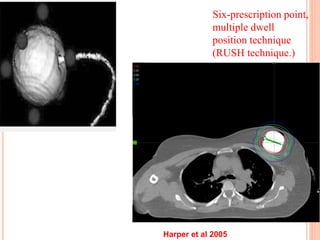

MammoSite PBI

MAMMOSITE CATHETER

Six-prescription point,

multiple dwell

position technique

(RUSH technique.)

Harper et al 2005